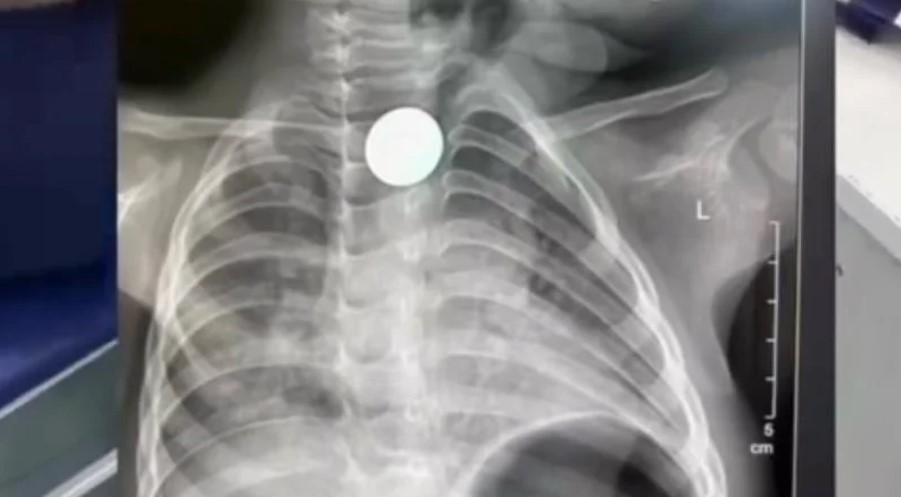

Маалым болгондой, кызыл өңгөчүнө тыйын тыгылып калган наристе Нарындан Бишкекке жөнөтүлгөн. Бөтөн зат кызыл өңгөчтүн экинчи физиологиялык тар жерине туруп калгандыктан, аны буга чейинки үч ооруканадан алып чыга албай коюшкан.

Ал эми тез жардам балдар клиникалык ооруканасынын дарыгерлери тыйынды операциясыз, Фолея катетерин колдонуу ыкмасы менен алып чыгышты. Учурда баланын абалы жакшы. Ал дароо үйүнө чыгарылып, өз алдынча тамактанып калды.